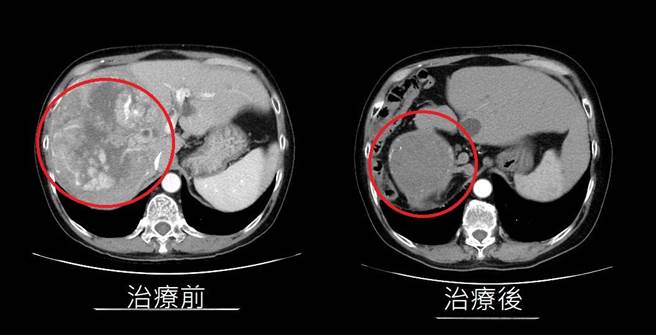

台中黄姓男子4年前因爆瘦、腹痛且易感疲倦就医,意外发现竟有1颗15公分大巨型肝臟肿瘤,经三合一疗法治疗顺利恢復。(亚大附医提供/潘虹恩台中传真)

台中黄姓男子4年前因爆瘦、腹痛且易感疲倦就医,意外发现竟有1颗15公分大巨型肝臟肿瘤,辗转多家医院都评估「生命仅剩2个月」,经与亚大医院医疗团队讨论后,採取「三箭齐发」策略,不仅恢復健康,癌指数更降到10以下,找回彩色人生。

经与癌症中心团队讨论后採用「标靶药物」、「光子刀放射治疗」以及「免疫治疗」等三合一疗法治疗,不但3个月后黄疸指数及癌症指数恢復正常,肿瘤也仅剩疤痕痕迹,近年来他稳定回诊追踪,无復发迹象。